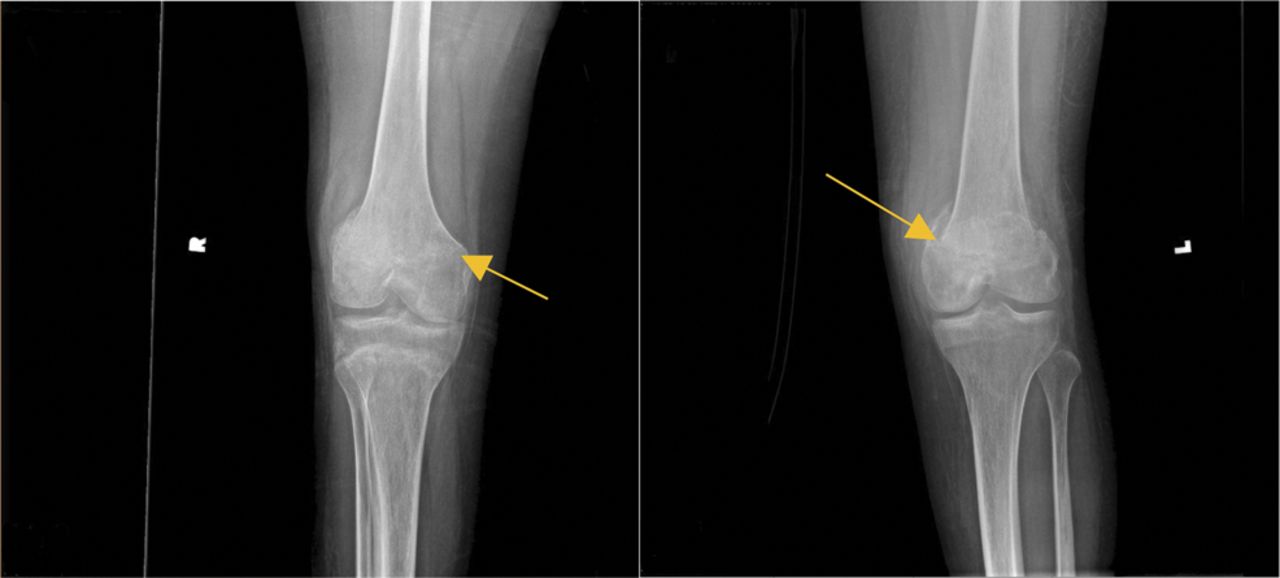

空气或脂肪栓子引起急性micropulmonary栓子紧随其后的大脑似乎栓子,鉴于呼吸之前投诉后的急性神经改变病人的下降。然而,最初,没有明显的栓子来源。没有明显的瘀伤的迹象显示骨折。在医院的第二天,出血点发达在腋窝和腹股沟。评估对隐匿性骨折骨调查显示新皮质step-offs沿横向方面的远端股骨metaphyses双边,可疑为轻微影响,nondisplaced,不完全骨折。随后的股骨和胫骨腓骨x射线证实了这些发现。整形外科手术把膝盖防盗控制系统。病人被诊断为脂肪栓塞综合征(包括脑脂肪栓塞)。虽然好处可用数据有限,甲基强的松龙(100毫克(四)日常管理1周,1周锥度。他的课程是复杂的脑水肿和脑积水,要求渗透疗法和外部心室排水位置。

SCI患者已知高长骨骨折的风险,这发生在一个年度发病率2% - -6%的人口。1,2在这种情况下,x射线显示只有轻微影响,nondisplaced骨折,提高是否SCI患者的脂肪栓塞的风险甚至轻微骨折。

SCI后,病人变得容易骨折由于严重减少损伤的骨密度水平以下。骨质流失的特点是去矿化作用的小梁晶格结构在股骨远端和胫骨近端骺,取而代之的是脂肪的骨髓。3这些患者的骨量影响因素包括损伤的程度和位置,肌肉痉挛状态、年龄、性别、受伤后负重活动,和持续时间。4,5在这种情况下,骨折的常见原因包括轮椅转移,把看不见的对象,和其他低效活动;重大创伤并不是必要的。1,2膝盖是经常在这些伤害的第一接触点,使它特别容易骨折。3双边股骨骨折增加脂肪栓塞的风险,发病率是33%与1% - -3%相比,在单一长骨骨折。6脂肪栓子通常建立在24 - 72小时的损伤。6脂肪栓塞综合征(FES)发生在脂肪栓子导致多系统器官衰竭,通常包括肺,皮肤,神经系统并发症。神经系统症状包括头痛、行为改变、癫痫、和改变意识。更罕见的表现包括剥皮姿态,脑水肿,脑积水,阵发性交感神经过度活跃。7系统性影响包括发热、心动过速、视网膜参与,黄疸,肾功能障碍、贫血、血小板减少症、炎症标志物升高。8在这种情况下,脂肪栓子心肌损伤可能导致新的心脏衰竭。